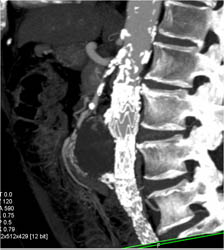

SVC Occlusion With Collaterals